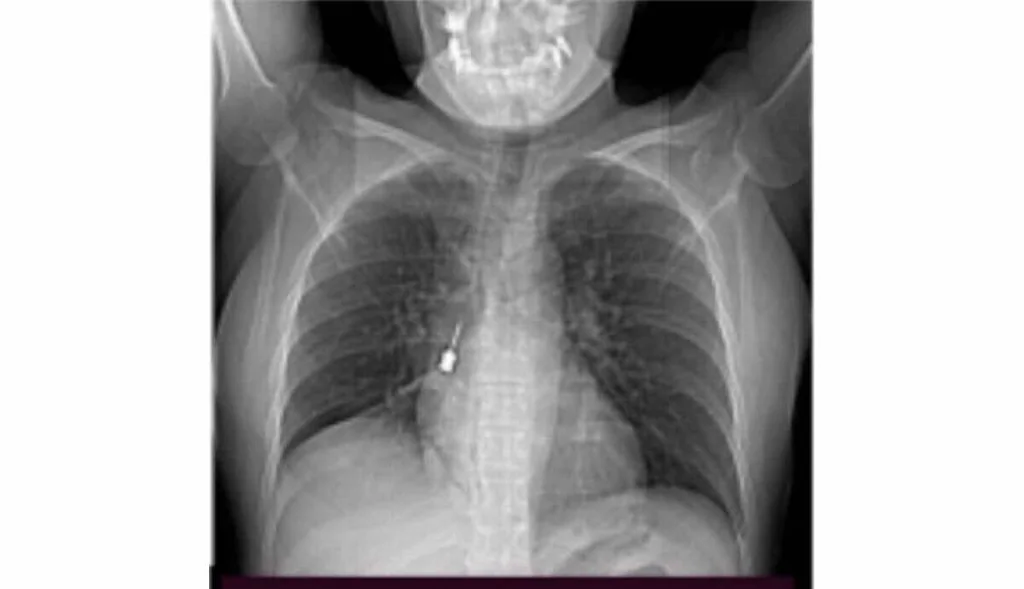

Un scanner a révélé « la présence d’un corps étranger métallique dangereux dans la bronche lobaire inférieure du poumon droit » associée à un pneumomédiastin. Compte tenu de la gravité, la patiente a été hospitalisée et transférée en salle d’opération pour une extraction du tournevis dentaire par bronchoscopie. L’outil a pu être retiré sans complication. « Le déroulement postopératoire, géré par l’excellente équipe de soins intensifs postopératoires (…) s’est déroulé normalement et la patiente a pu quitter l’hôpital en excellente santé », s’est encore félicité l’établissement.